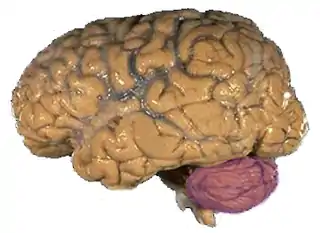

![]() | ||

![]() Cerebelo en púrpura. Sección sagital de un encéfalo en una RMN. | ||